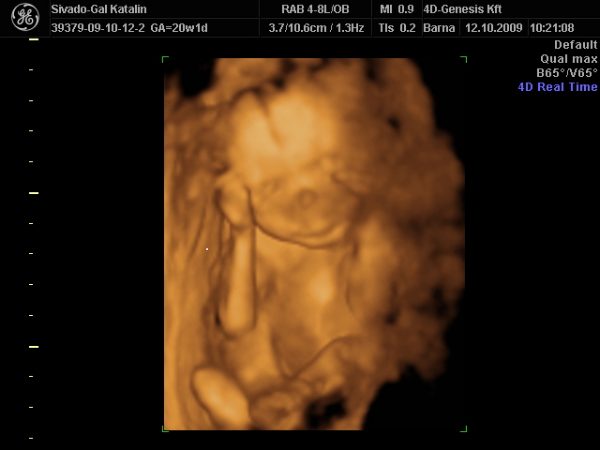

Az ígért kép a kis szégyenlős lányunkról.

Kép Lilien, amennyit megmutatott magából